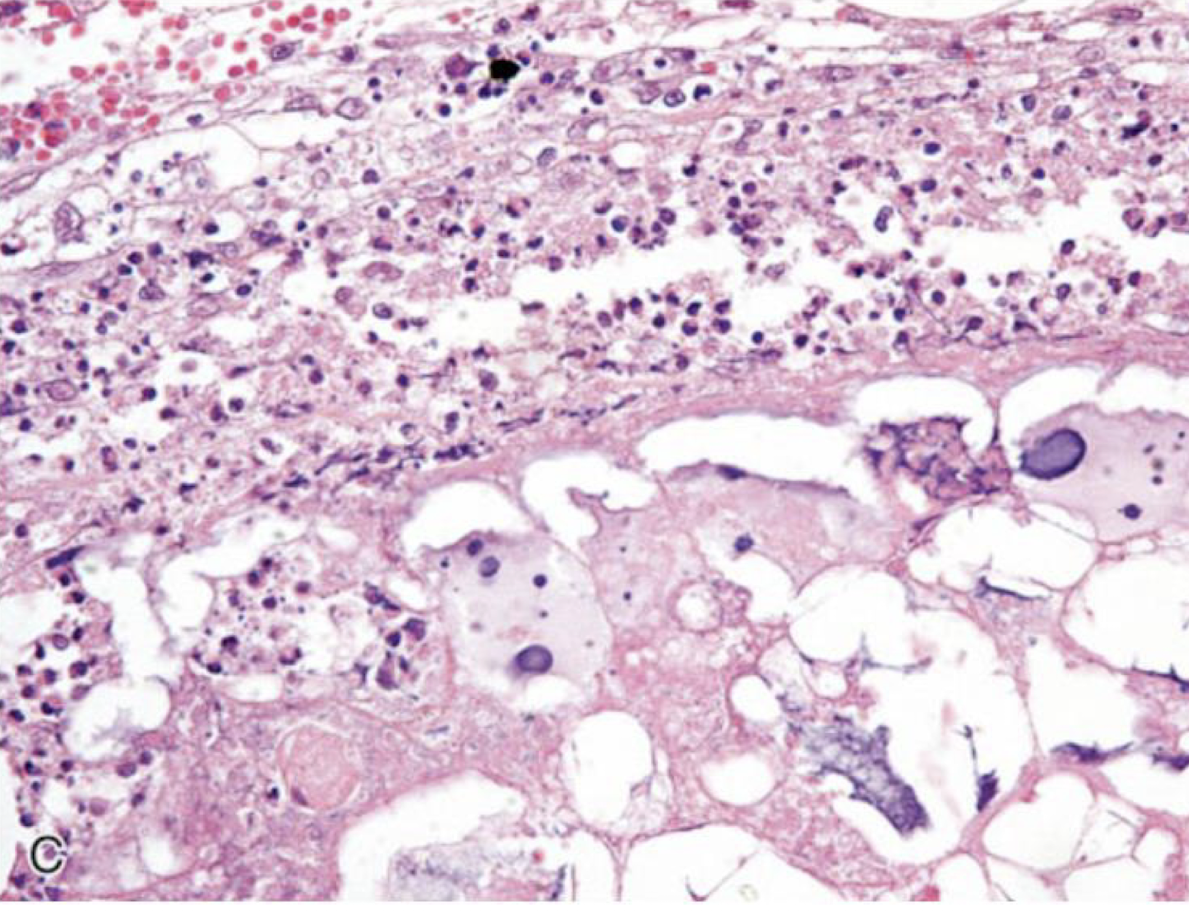

What is this an image of?

caseous necrosis

What can older lesions of caseous necrosis do?

organize and form laminations